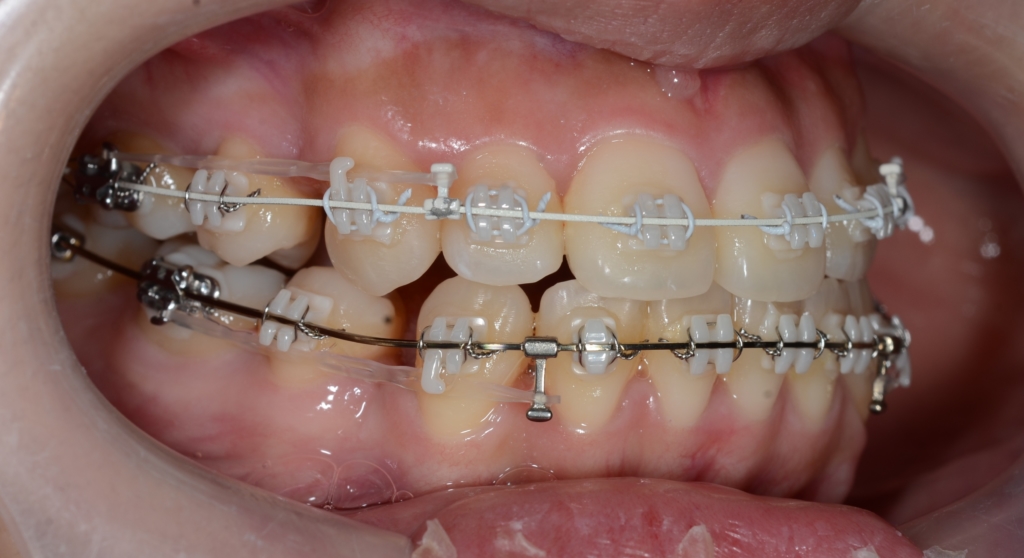

治療により正中は合うのですが、仕上げのために他の微調整をしていると、気付いたらまた正中がズレる・・・

他のやり方でと考え、従来よく用いられて顎間ゴムを約3か月間行い正中を合わせても、また・・・

という状況が繰り返されました。

患者さんの方から、「見た目は大満足!だし、噛み合わせもズレていると言うが何の問題もなく美味しくご飯を食べられている! ココまで来たら早く矯正装置を外したい。」という優しい言葉があり、忸怩たる思いはありましたが、甘えることにしました。